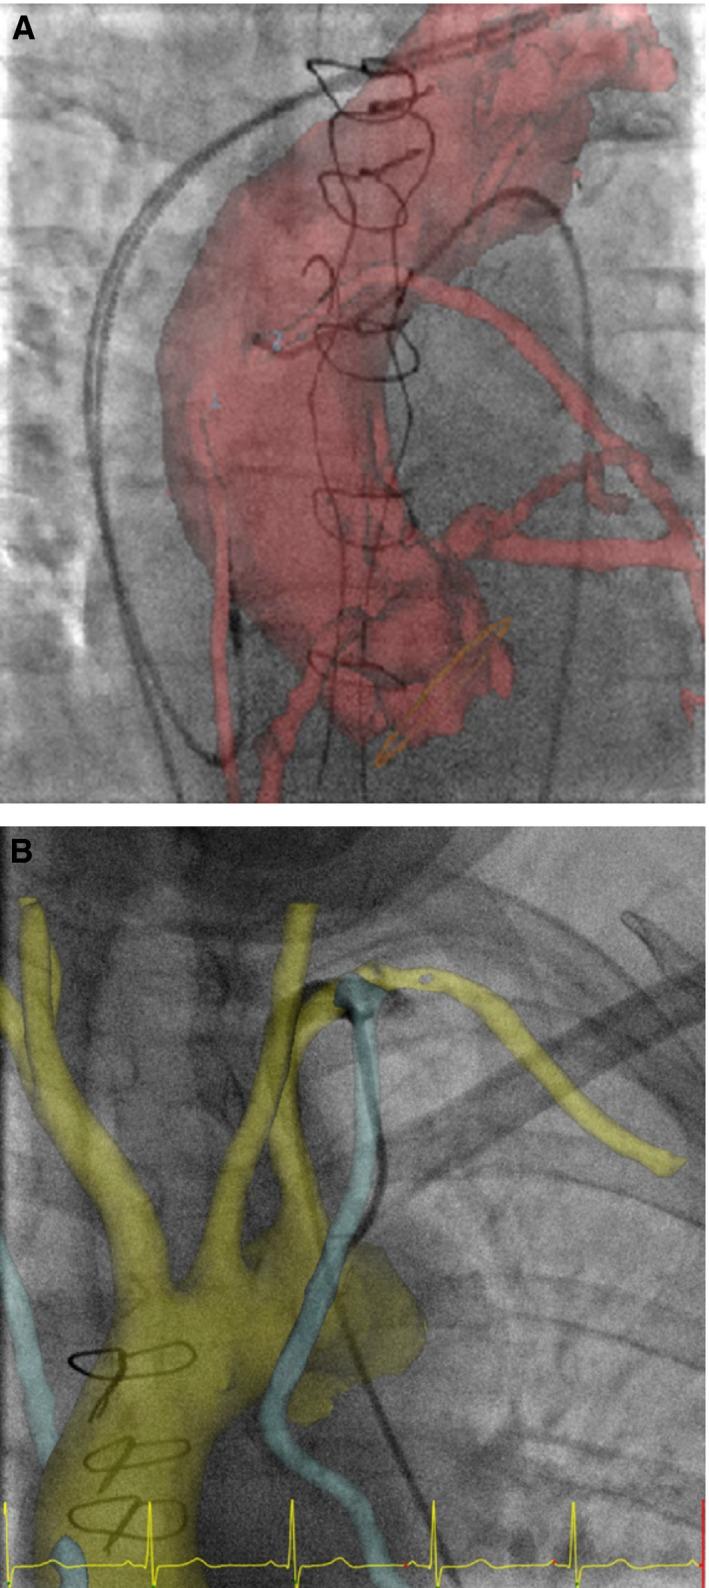

Coronary angiography is more complex in patients with coronary artery bypass grafts (CABG). Image fusion is a new technology that allows the overlay of a computed tomography (CT) three-dimension (3D) model with fluoroscopic images in real time.

This single-center prospective study included 66 previous CABG patients undergoing coronary and bypass graft angiography. Image fusion coronary angiographies (fusion group, 20 patients) were compared to conventional coronary angiographies (control group, 46 patients). The fusion group included patients for whom a previous chest CT scan with contrast was available. For patients in this group, aorta and CABG were reconstructed in 3D from CT acquisitions and merged in real time with fluoroscopic images. The following parameters were compared: time needed to localize the CABG; procedure duration; air kerma (AK); dose area product (DAP); and volume of contrast media injected. Results are expressed as median. There were no significant differences between the 2 groups in patient demographics and procedure characteristics (access site, number of bypass to be found, and interventional cardiologist's experience). The time to localize CABG was significantly shorter in the fusion group (7.3 versus 12.4 minutes; P=0.002), as well as the procedure duration (20.6 versus 25.6 minutes; P=0.002), AK (610 versus 814 mGy; P=0.02), DAP (4390 versus 5922.5 cGy·cm(2); P=0.02), and volume of iodinated contrast media (85 versus 116 cc; P=0.002).

CONCLUSIONS

3D image fusion improves the CABG detection in coronary angiography and reduces the time necessary to localize CABG, total procedure time duration, radiation exposure, and volume of contrast media.

冠状动脉搭桥术(CABG)患者的冠状动脉造影更为复杂。图像融合是一项新技术,可将计算机断层扫描(CT)三维(3D)模型与荧光透视图像实时叠加。

这项单中心前瞻性研究纳入了66例曾接受CABG且正在接受冠状动脉和搭桥血管造影的患者。将图像融合冠状动脉造影(融合组,20例患者)与传统冠状动脉造影(对照组,46例患者)进行比较。融合组纳入了有既往胸部增强CT扫描的患者。对于该组患者,从CT采集数据中重建主动脉和CABG的三维模型,并与荧光透视图像实时融合。比较以下参数:定位CABG所需时间、手术持续时间、空气比释动能(AK)、剂量面积乘积(DAP)以及注入的造影剂体积。结果以中位数表示。两组患者的人口统计学特征和手术特点(穿刺部位、需查找的搭桥血管数量以及介入心脏病专家的经验)无显著差异。融合组定位CABG的时间显著缩短(7.3分钟对12.4分钟;P = 0.002),手术持续时间也显著缩短(20.6分钟对25.6分钟;P = 0.002),AK(610对814 mGy;P = 0.02),DAP(4390对5922.5 cGy·cm²;P = 0.02)以及碘化造影剂体积(85对116 cc;P = 0.002)。

结论

三维图像融合可改善冠状动脉造影中CABG的检测,并减少定位CABG所需时间、总手术时间、辐射暴露以及造影剂体积。